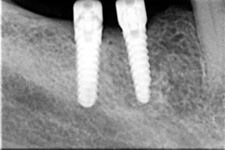

Zavedení implantátů do kosti je většinou ambulantní chirurgický výkon, srovnatelný s vytržením zubu a většinou se provádí v lokální anestézii. Ve výjimečných případech je možné použít i analgosedaci či celkovou narkózu. Operaci provádí zubní lékař-implantolog při dodržení všech podmínek sterility pro operaci. Nástroje pro tuto operaci jsou konstruovány tak, aby výkon byl šetrný vůči kosti a zavedení implantátu bylo provedeno ve velmi krátké době. Díky kvalitní anestézii je výkon nebolestivý. Aby byl pooperační otok co nejmenší, je potřeba operovanou oblast chladit, dle poučení ošetřujícího lékaře. Lékař také ordinuje podle potřeby léky na bolest, případně antibiotika.

Podle plánu může být pacient ošetřen po dobu vhojování implantátů předem domluvenou a zhotovenou provizorní náhradou.

Průměrná doba hojení implantátů před provedením definitivního protetického ošetření je 3-4 měsíce, v případech, kde je nutné doplnit chybějící kost (různé metody, postupy a materiály) – tzv. augmentace) se může doba hojení prodloužit na 8-12 měsíců. S tím je pacient vždy předem seznámen svým lékařem.